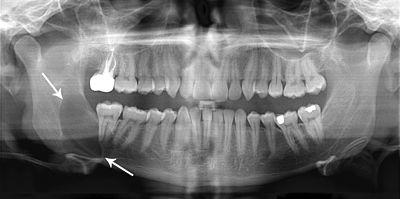

Massive keratocystic odontogenic tumour with impacted wisdom teeth superficial to lesion

As the condition is quite rare, opinions among experts about how to treat KCOTs differ.

KCOTs are thought to arise from the dental lamina and are associated with impacted teeth. Multiple odontogenic keratocysts are a feature of nevoid basal cell carcinoma syndrome. Odotogenic Keratocysts are derived from the remnants of the Dental Lamina.